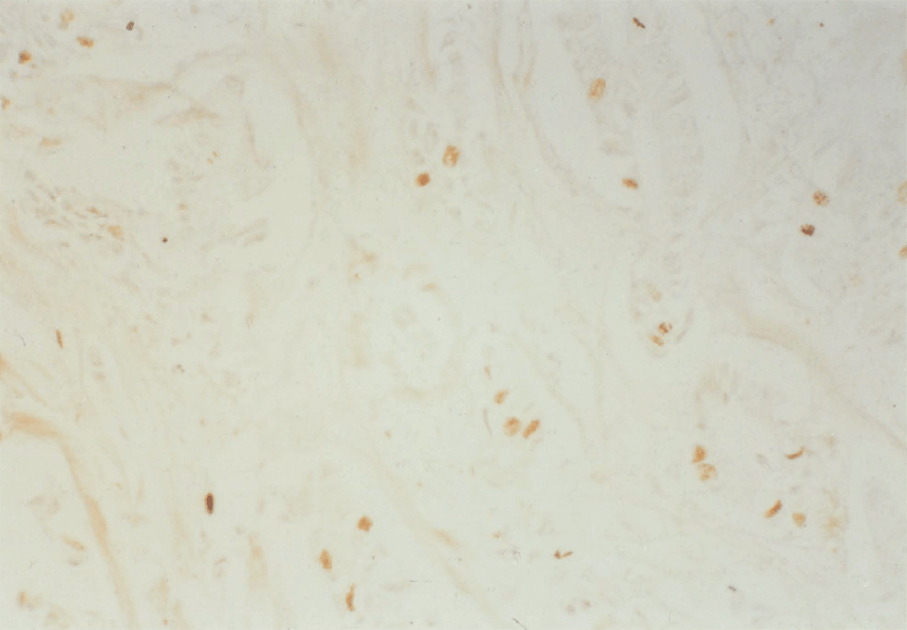

8:6. Photomicrograph of polyposis coli mucosa stained for p62c-myc protein.

8:7. Photomicrograph of polyposis coli mucosa stained for p62c-myc protein.